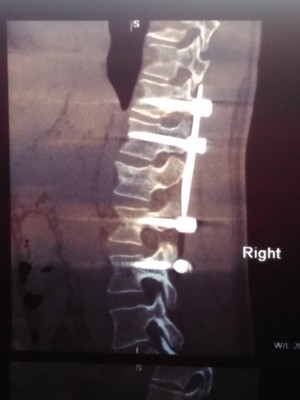

20 мая в результате падения с высоты получил взрывной перелом L1 типа В3, полное вертикальное и горизонтальное расщепление со смещением отломков задне-верхнего угла до 3,5 мм и переднего до 4,5 мм. А также вертикальный перелом Th12 типа В2 без смещения и расщепления. Через 5 дней была проведена операция ТПФ Th11,12-L2,3

7 августа (через 2,5 месяца) была сделана повторное КТ (снимки которого прикладываю). Со слов оперирующего доктора позвонок L1 не срастается, мелкие осколки "растворились", требуется операции по замене L1. В описании написано: частичный остеолиз краев фрагментов, с наличием диастазов до 5-6 мм.

12.jpg

11.jpg

01.jpg